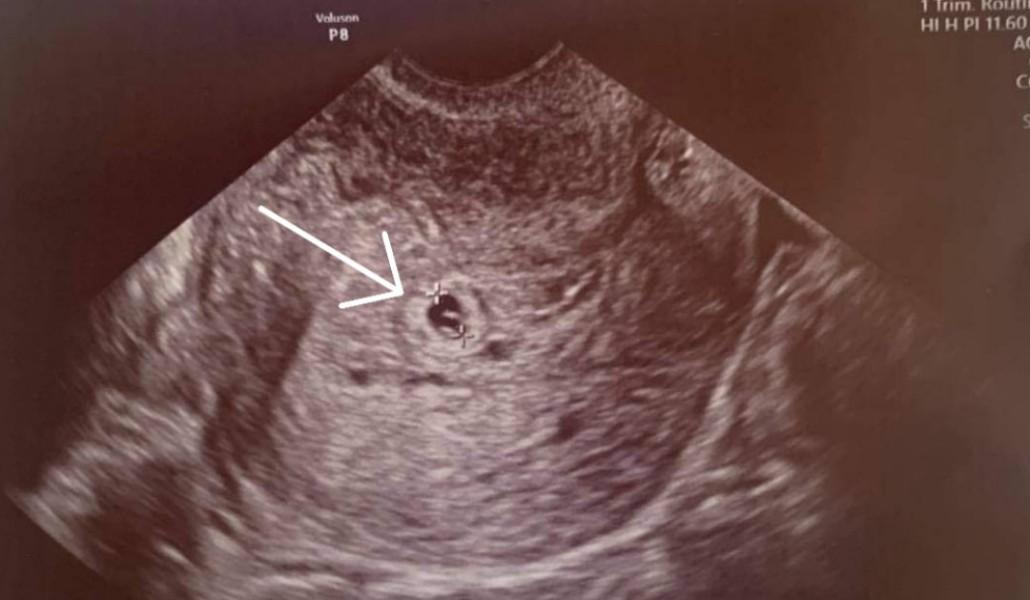

44-օրյա պատերազմում եղբորը կորցրած կինը հղիացել է երկար տարիների անպտղությունից հետո

44 օրյա պատերազմում եղբորը կորցրած պացիենտը հղիացել է երկար տարիների անպտղությունից հետո։

Աննկարագրելի հուզիչ էր մոնիտորին տեսնել այս փոքրիկ, բայց մի ամբողջ ընտանիքի նոր կյանքի լույս տվող կետը»։